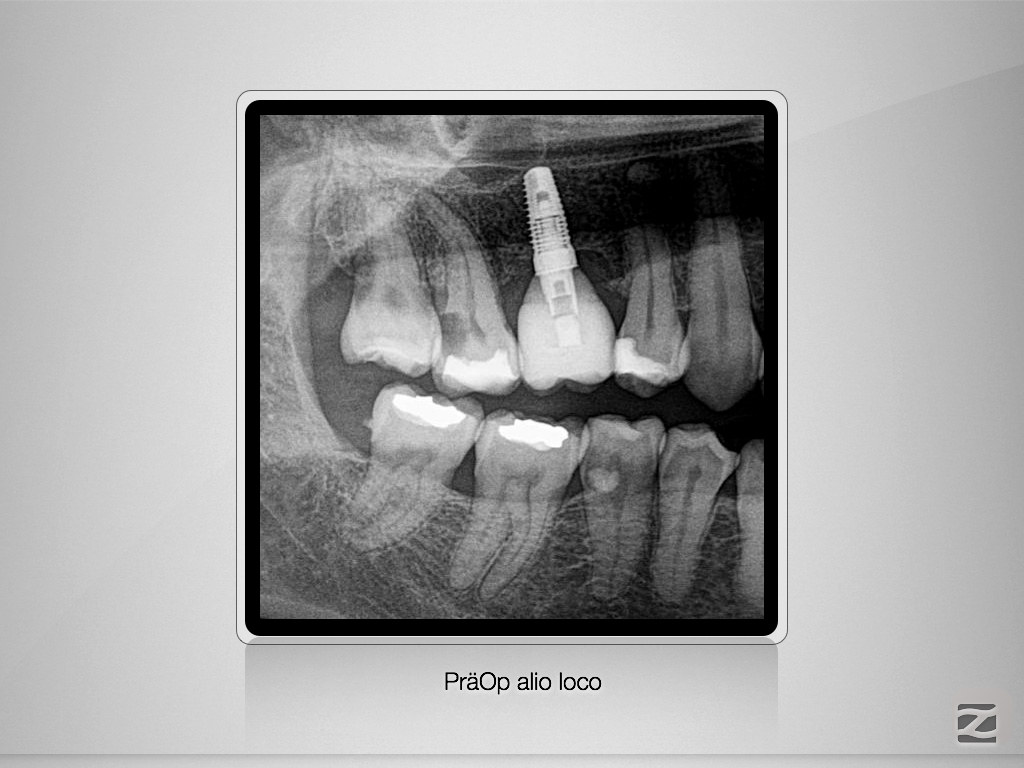

Gewusst, wo’s lang geht.